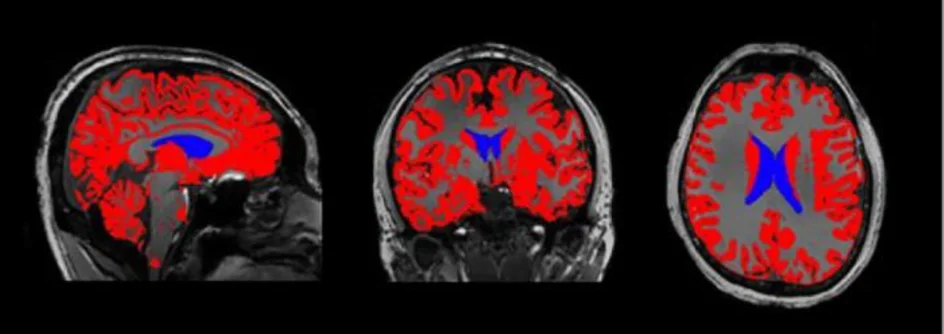

اعتمد الباحثون على التصوير بالرنين المغناطيسي عالي الدقة (MRI) لمقارنة أدمغة أشخاص أُصيبوا سابقا بكوفيد-19 مع آخرين لم يتعرضوا للفيروس ، واستخدم الفريق ما يُعرف بـالتصوير متعدد الأنماط، وهي تقنية متقدمة تسمح بتحليل:

أظهرت نتائج التصوير وجود اختلافات واضحة في:

بنية أنسجة الدماغ

شدة الإشارات العصبية

التوازن الكيميائي العصبي

ولم تقتصر هذه التغيرات على المصابين بـكوفيد طويل الأمد (Long COVID) فقط، بل ظهرت أيضا لدى أشخاص لا يعانون من أي أعراض حالية ويعتقدون أنهم تعافوا بشكل كامل.